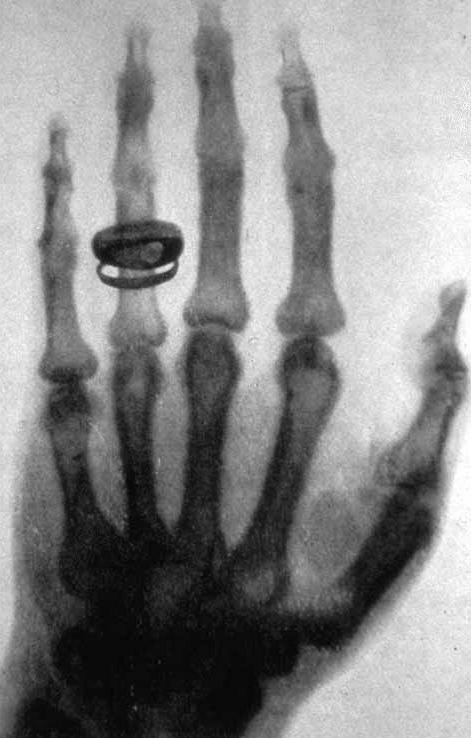

La tarde del viernes 8 de noviembre de 1895, la esposa del físico alemán Wilhelm Conrad Roentgen, Anna, oyó la llamada de su marido y acudió para ver qué ocurría. Wilhelm le pidió que pusiera su mano sobre un extraño aparato y que la mantuviera allí quieta durante más de quince minutos. A continuación, le mostró lo que parecía ser una fotografía en la que se podía apreciar con nitidez todos los huesos de su mano y donde se podía ver con claridad su anillo de compromiso. Anna se sintió fascinada y asustada al mismo tiempo; el poder distinguir sus huesos en la primera radiografía de la historia, la hizo sentirse cercana a la muerte. En poco tiempo, los rayos X se convirtieron en parte esencial de la medicina, pero también de la arqueología, el arte o la ingeniería, y se convirtieron en parte esencial de la seguridad en aeropuertos o edificios gubernamentales. Sorprendentemente, solo dos años después de su descubrimiento, ya había un médico que ofrecía el servicio de radiografía en Galicia. Un gallego que fundó uno de los primeros institutos antirrábicos de España y contribuyó a evitar que la terrible peste bubónica regresara de nuevo a nuestro país. Ángel Cobián Areal.

La mano de Anna, primera radiografía de la historia. https://es.wikipedia.org